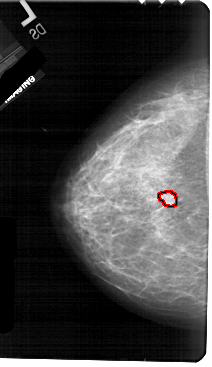

A_1725_1.LEFT_CC

LEFT_CC LINES 5491 PIXELS_PER_LINE 3166 BITS_PER_PIXEL 12 RESOLUTION 43.5 OVERLAY

FILE: A_1725_1.LEFT_CC.OVERLAY

TOTAL_ABNORMALITIES 1

ABNORMALITY 1

LESION_TYPE MASS SHAPE FOCAL_ASYMMETRIC_DENSITY MARGINS ILL_DEFINED

ASSESSMENT 4

SUBTLETY 3

PATHOLOGY MALIGNANT

TOTAL_OUTLINES 1

BOUNDARY